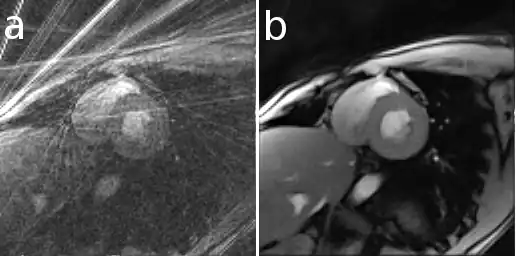

Here is an example that illustrates the benefits of iterative image reconstruction for cardiac MRI.[21]

In Magnetic Resonance Imaging it can be used to reconstruct images from data acquired with multiple receive coils and with sampling patterns different from the conventional Cartesian grid[17] and allows the use of improved regularization techniques (e.g. total variation)[18] or an extended modeling of physical processes[19] to improve the reconstruction. For example, with iterative algorithms it is possible to reconstruct images from data acquired in a very short time as required for real-time MRI (rt-MRI).[6]